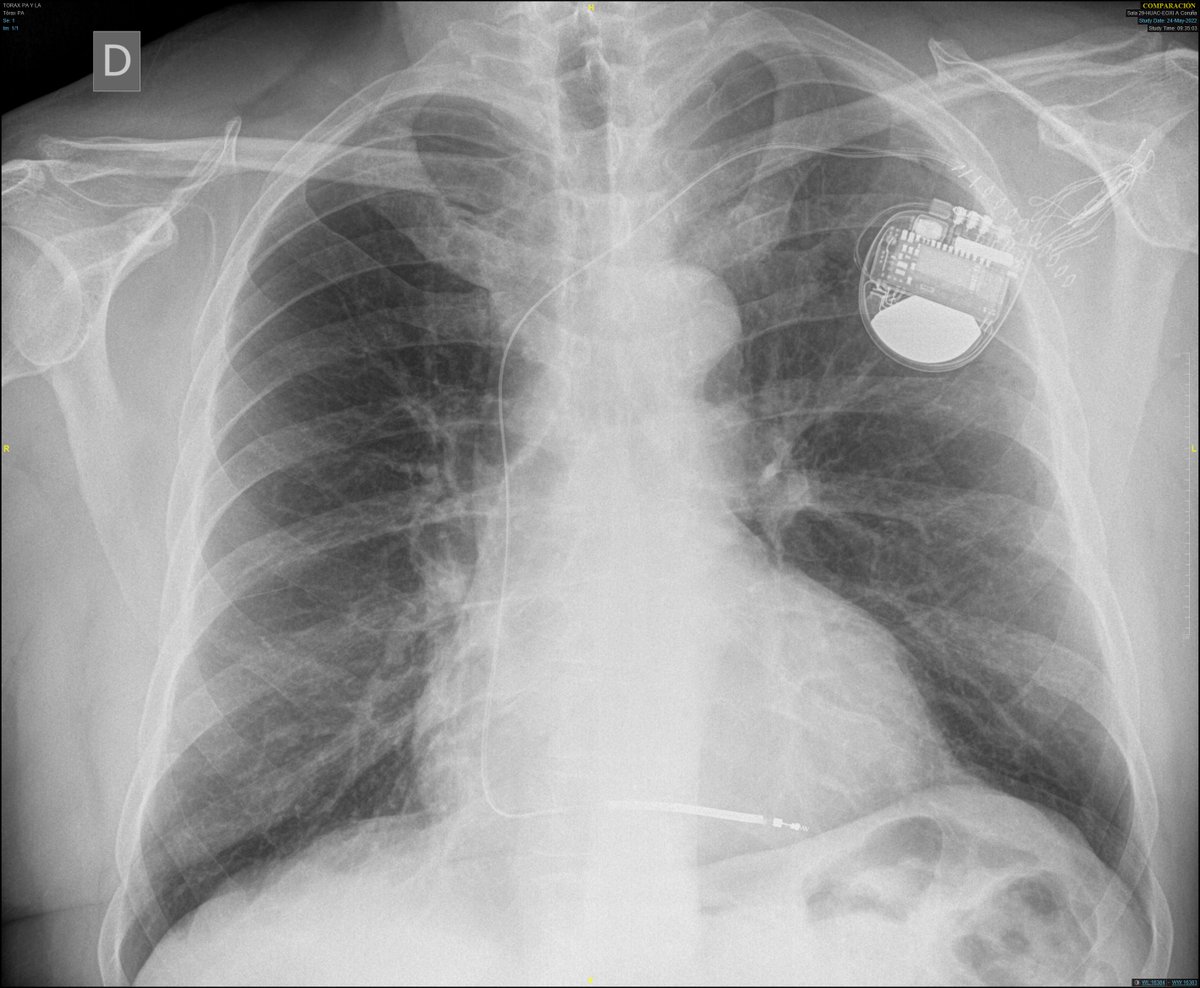

Safety and efficacy of intracardiac echocardiography in #AtrialFibrillation ablation: A meta-analysis